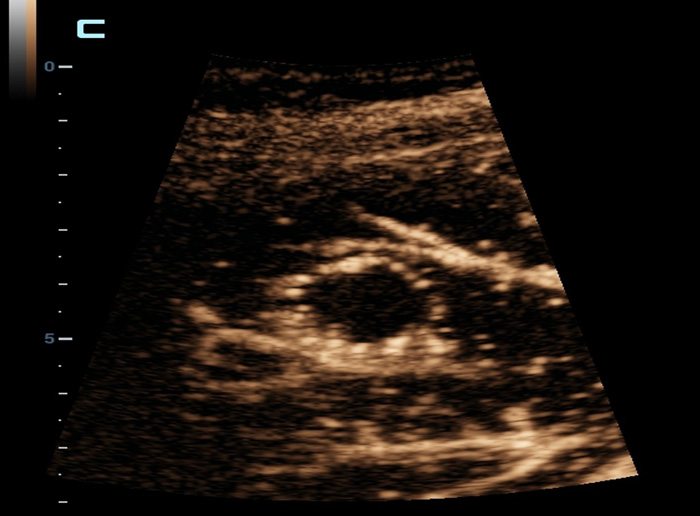

Ultra-Micro-angiografie (UMA)

UMA verbetert het diagnostische vertrouwen door de zichtbaarheid van de bloedstromen uit te breiden tot op het kleinste vaatniveau, met een superieure gevoeligheid en resolutie van de bloedstroom.

sUMA Nier

pUMA Borstmassa

sUMA Schildklierkanker

Borstmassa cUMA

Borstmassa

Leverlaesies

Lymfeklieren sUMA

MSK laesie sUMA

Testikel UMA

Varicocele beglazing sUMA

Borstmassa CEUS

Nier PUMA

L15-3WU Borstmassa E Compare

Levermassa CEUS